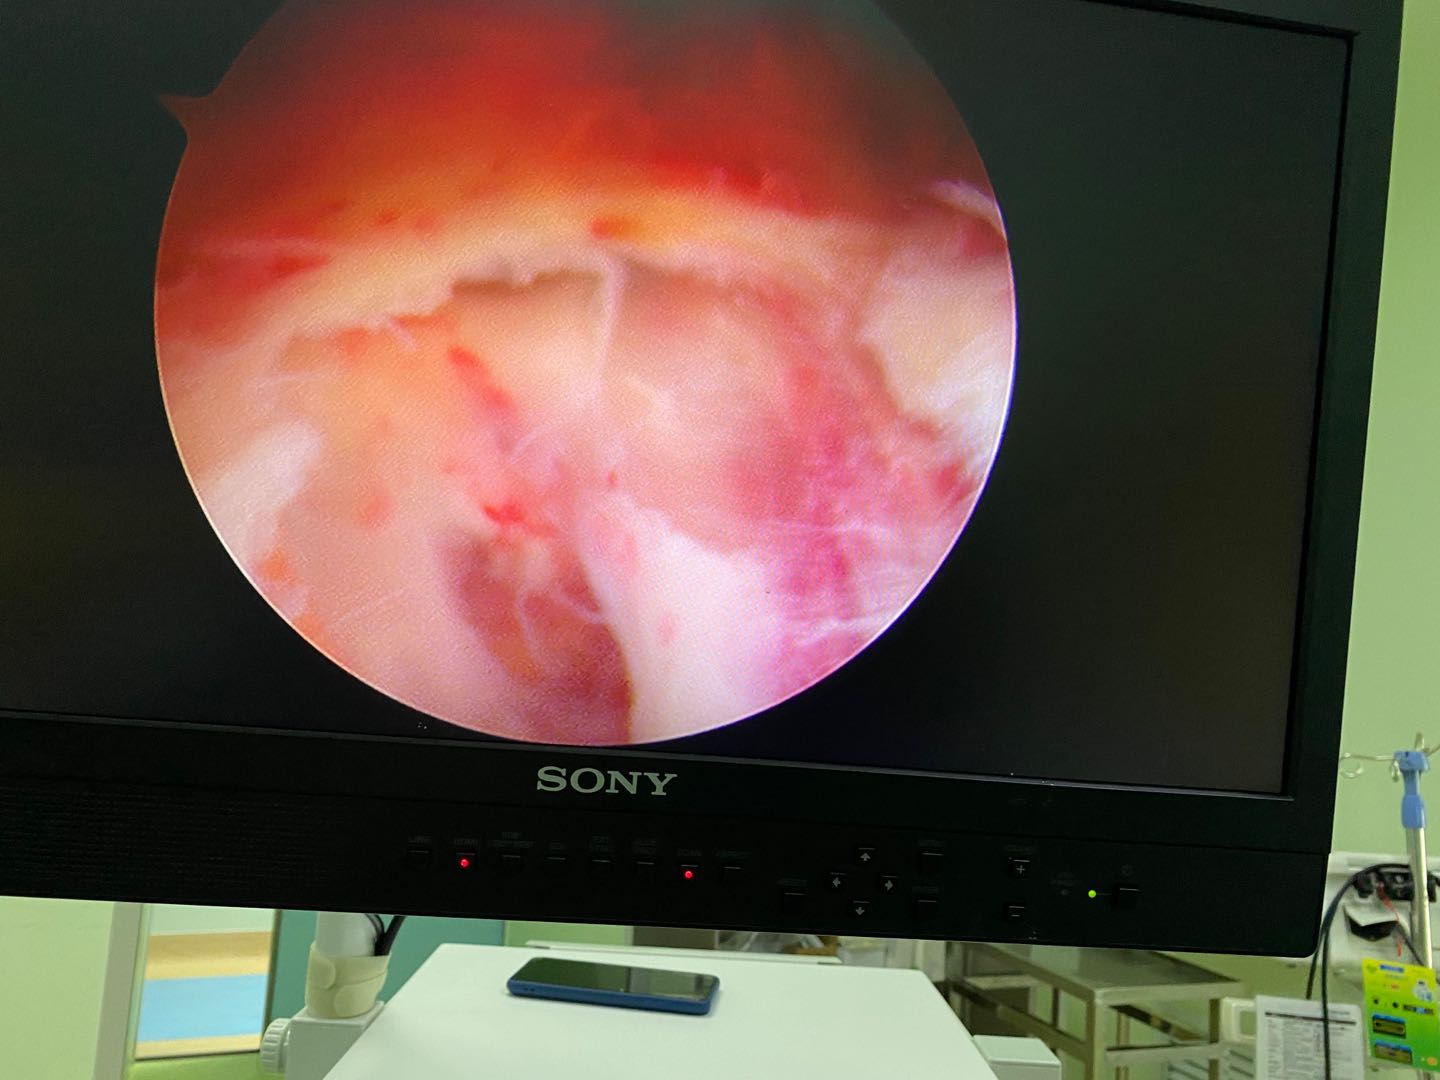

图4a 关节镜手术

4.关节镜手术仅需要2-3个0.5cm的小孔就能完成,术中出血少,在直视视野下能够彻底切除囊肿,保护神经,安全性更高,术后基本无痛,术后第二天即可下床活动,伤口愈合后基本看不见疤痕。

图4b 关节镜显示坐骨结节囊肿